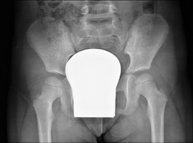

- Pelvis X-ray

This procedure uses X-ray imaging to examine the pelvis, especially the pelvic bones.